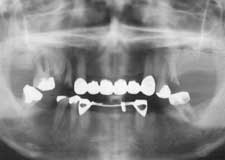

Hさん 初診時 53歳 男性

50歳頃まではもう少し歯があったそうですが、歯科医院に行くたびに「歯槽膿漏です」といわ れて抜歯。60歳まで何とか総入れ歯にしたくないという

Hさん 19年後 72歳

上顎の補綴処置と左下の親知らずを抜歯。歯槽膿漏の手術を行うことなく月に1度の歯石除去 を継続して行った結果、初診時から大きく変化することなく19年を経過しました